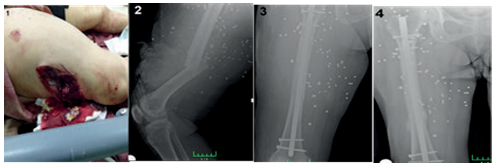

The average surgery duration for the seven humeral fractures was 2.14 hours (range 1.5-3 hours). The mean time to union was 10.1 weeks (range 8-12 weeks). One of the seven humeral fractures (14.2%) resulted from low-velocity, while six were due to high-velocity gunshot injuries. All patients had isolated humeral fractures, and all were smokers.

One patient (14.28%) developed an early superficial infection in the postoperative period, leading to debridement. After debridement, antibiotic therapy, and dressing changes, the infection resolved. No patient developed a deep infection, and there were no cases of nonunion (Table 3). Representative preoperative and postoperative radiographs of humeral fractures treated with intramedullary nailing are shown in Figure 2.

The optimal protocol for the treatment of open humerus fractures has not been clearly stated in the literature. Open humerus shaft fractures should be considered as a separate entity with their treatment protocol.21 There is currently insufficient research on humerus fractures resulting from gunshot injuries treated with IMN. In a case series involving 38 humerus fractures treated with external fixation, including 35 caused by low-velocity gunshot injuries, bone union occurred between 12 and 24 weeks (average 16 weeks). Two patients required bone grafting due to delayed union. Nonunion occurred in two patients (5%). Five patients had superficial nail tract infections, two had deep wound infections, and one had bone infection.22 We applied locked intramedullary nails to 7 humerus shaft fractures resulting from gunshot injuries. The average union time was 10.1 weeks. We observed no cases of nonunion. One patient (14%) developed a superficial infection, which resolved after debridement and antibiotic therapy. There were no cases of deep infection or nonunion. Operating on all our patients within the first 8 hours may have reduced the infection rate. We attribute our shorter union times and achieving union in all patients to the low infection rates and the use of intramedullary nails.

Figure 2

Figure 2. Humerus Fracture - Preoperative Radiograph - Postoperative Radiograph of Humerus Intramedullary Nailing